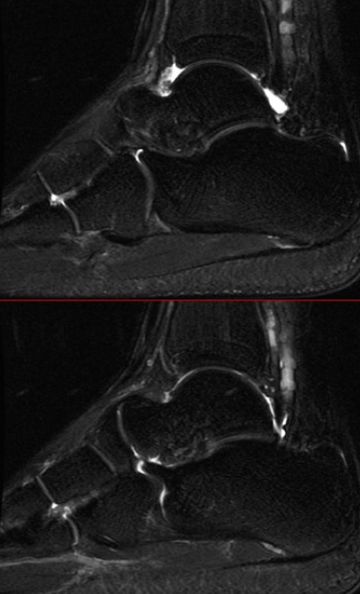

二、骨软骨损伤

好发于距骨前外侧、后内侧,尤其是后内侧,与内翻损伤相关。

MRI表现为软骨下骨质内斑片状或囊状T1WI低信号、STRI高信号影,伴或不伴小骨软骨碎片的分离、移位。